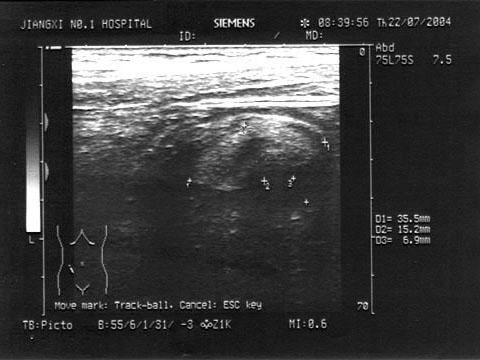

问题 患者,女性,29岁,右下腹持续性剧痛数小时,伴恶心、呕吐。PE:右下腹饱满,可扪及一压痛性包块,边界不清;WBC:18×10/L,尿HCG(Ⅲ),麦氏点压痛,反跳痛(+)。结合超声声像图,最可能的诊断为?(?) {图1}

选项 A.异位妊娠破裂 B.阑尾炎 C.输尿管结石 D.急性输卵管炎 E.肠梗阻

答案 B